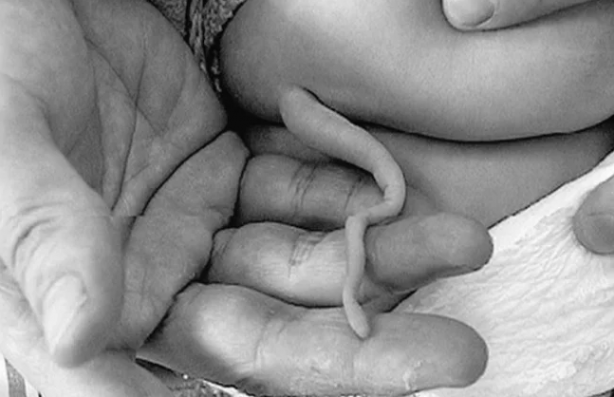

Meksika’da ismi açıklanmayan bir kız bebek 6 cm uzunluğunda bir kuyrukla dünyaya geldi.

Tamamen saç ve deriden kaplı bir yapıyla dünyaya gelen kız çocuğu milyonda bir kez görülebilecek tıbbi bir vakaya imza atmayı başardı. Doktorlar tüm incelemelerin sonunda ise kuyruğu bedeninden cerrahi işlemle kesti.

Meksika’nın kuzeydoğusundaki bir kırsal hastanede sezaryenle dünyaya gelen bir bebek tüylü kuyruğu nedeniyle manşetlere çıktı. Journal of Pediatric Surget’ye göre, çocuğun daha önce radyasyona maruz kalma öyküsü veya hamilelik sırsında enfeksiyon öyküsü bulunmuyordu. 20’li yaşlarında sağlıklı iki ebeveynin kızı olarak dünyaya gelen bebeğin kuyruğu yaklaşık 6 cm uzunluğunda ve 3 ila 5 mm arasında değişen bir yarı çapa sahipti.

Kuyruğa benzeyen yapının saç ve deriyle kaplı olduğu fark edildikten sonra röntgen çektiler. Kuyrukta herhangi bir anormallik veya kemik yapısı bulgusu bulamadılar. Bu, kuyruğun zamanla vücuttaki tüm kullanımlarını yitirmiş bir apendiks anlamında işlevsiz bir kuyruk değil, “gerçek bir kuyruk” olduğu belirlendi. Doktorlar vakayı "Son derece nadirdir" şeklinde tanımladı.